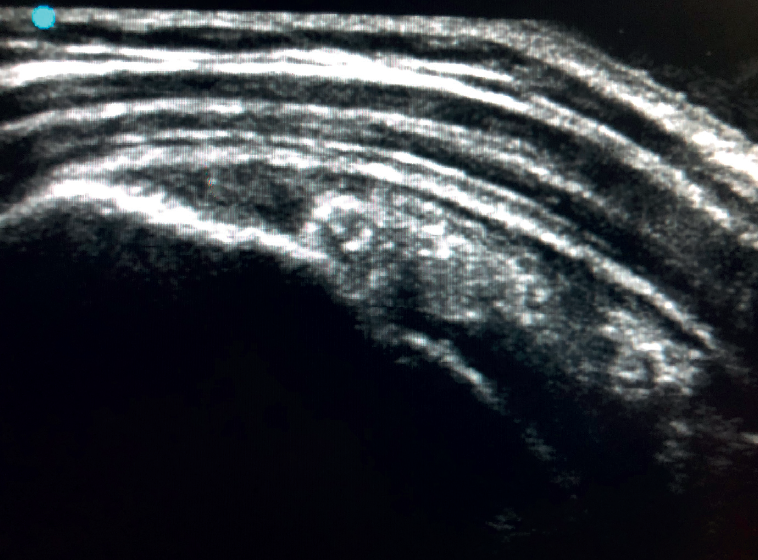

La imagen ecográfica propia de una tendinosis corresponde con un engrosamiento local o difuso acompañado de un aspecto hipoecogénico y heterogéneo del tendón (Figura 3). Una línea fina e hipoecoica mayor de 2 mm de grosor entre el tendón del supraespinoso y la grasa subdeltoidea corresponde con una bursitis subacromiosubdeltoidea y la presencia de líquido en la bursa se relaciona con elevada probabilidad con una lesión parcial o completa del tendón del supraespinoso(26). Para mayor exactitud diagnóstica y diferenciar un proceso inflamatorio de una pequeña cantidad normal de fluido en la bursa, en las bursitis, tenosinovitis y tendinitis hay presencia de zonas hiperecoicas con áreas de aumento de flujo en el Doppler. Las roturas parciales, tanto bursales como articulares, se ven como una discontinuidad hipoecoica en el tendón que no cambia al modificar la inclinación de la sonda ni en el eje largo del tendón ni en el corto(19). Este último aspecto es importante para no confundir lesiones parciales con el fenómeno de anisotropía, que es un cambio en el comportamiento del tejido en función del ángulo de incidencia del ultrasonido(27) (Figura 4).

Figura 4. Fenómeno de anisotropía en la inserción del tendón del supraespinoso. No confundir con lesión de espesor parcial.